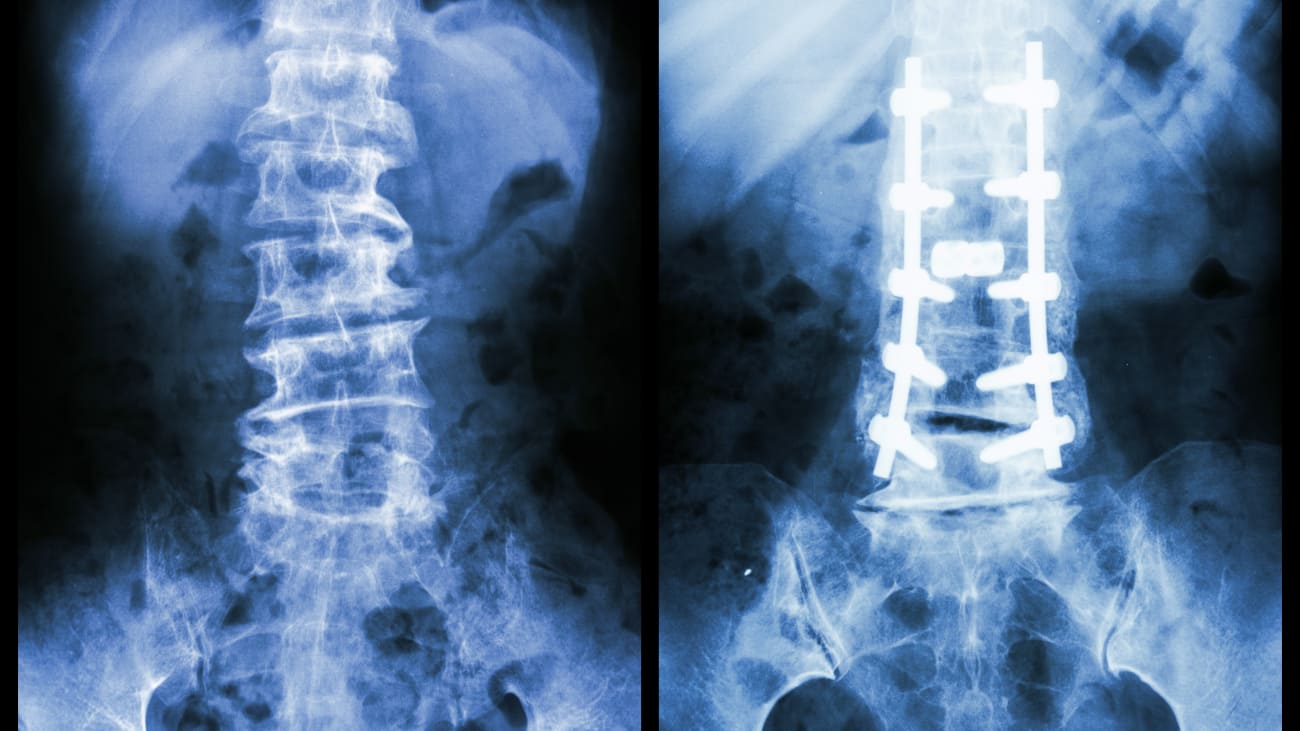

Adolescent Scoliosis and Adult Spinal Deformity

This presentations discusses the diagnosis and treatment of adolescent scoliosis and adult spinal deformity including information on how to classify spinal deformity, cutting edge research and several case studies.